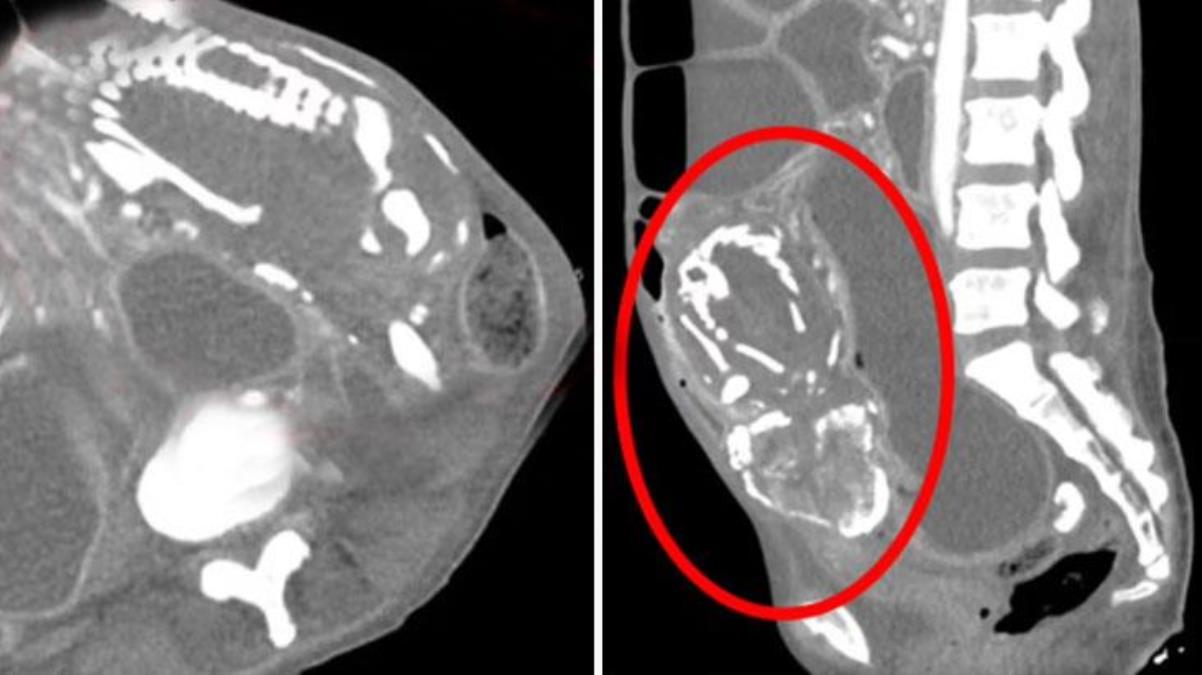

Dünya Dünya üzerindeki 300’üncü vaka! Taşlaşan cenin, 50 yaşındaki kadını öldürdü 3 yıl once eklendi Haber Merkezi